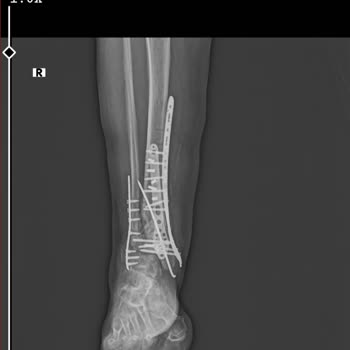

07.11.2025 tarihinde saat 03:40’ta, sınavlarım nedeniyle özellikle o saate almak zorunda kaldığım bir randevu ile Kocaeli Derince Eğitim ve Araştırma Hastanesi Rekonstrüktif ve Estetik Cerrahi polikliniğine gittim. Yabancı isimli kadın doktora muayene oldum. Doktor hanıma ameliyat olmak istediğimi b...